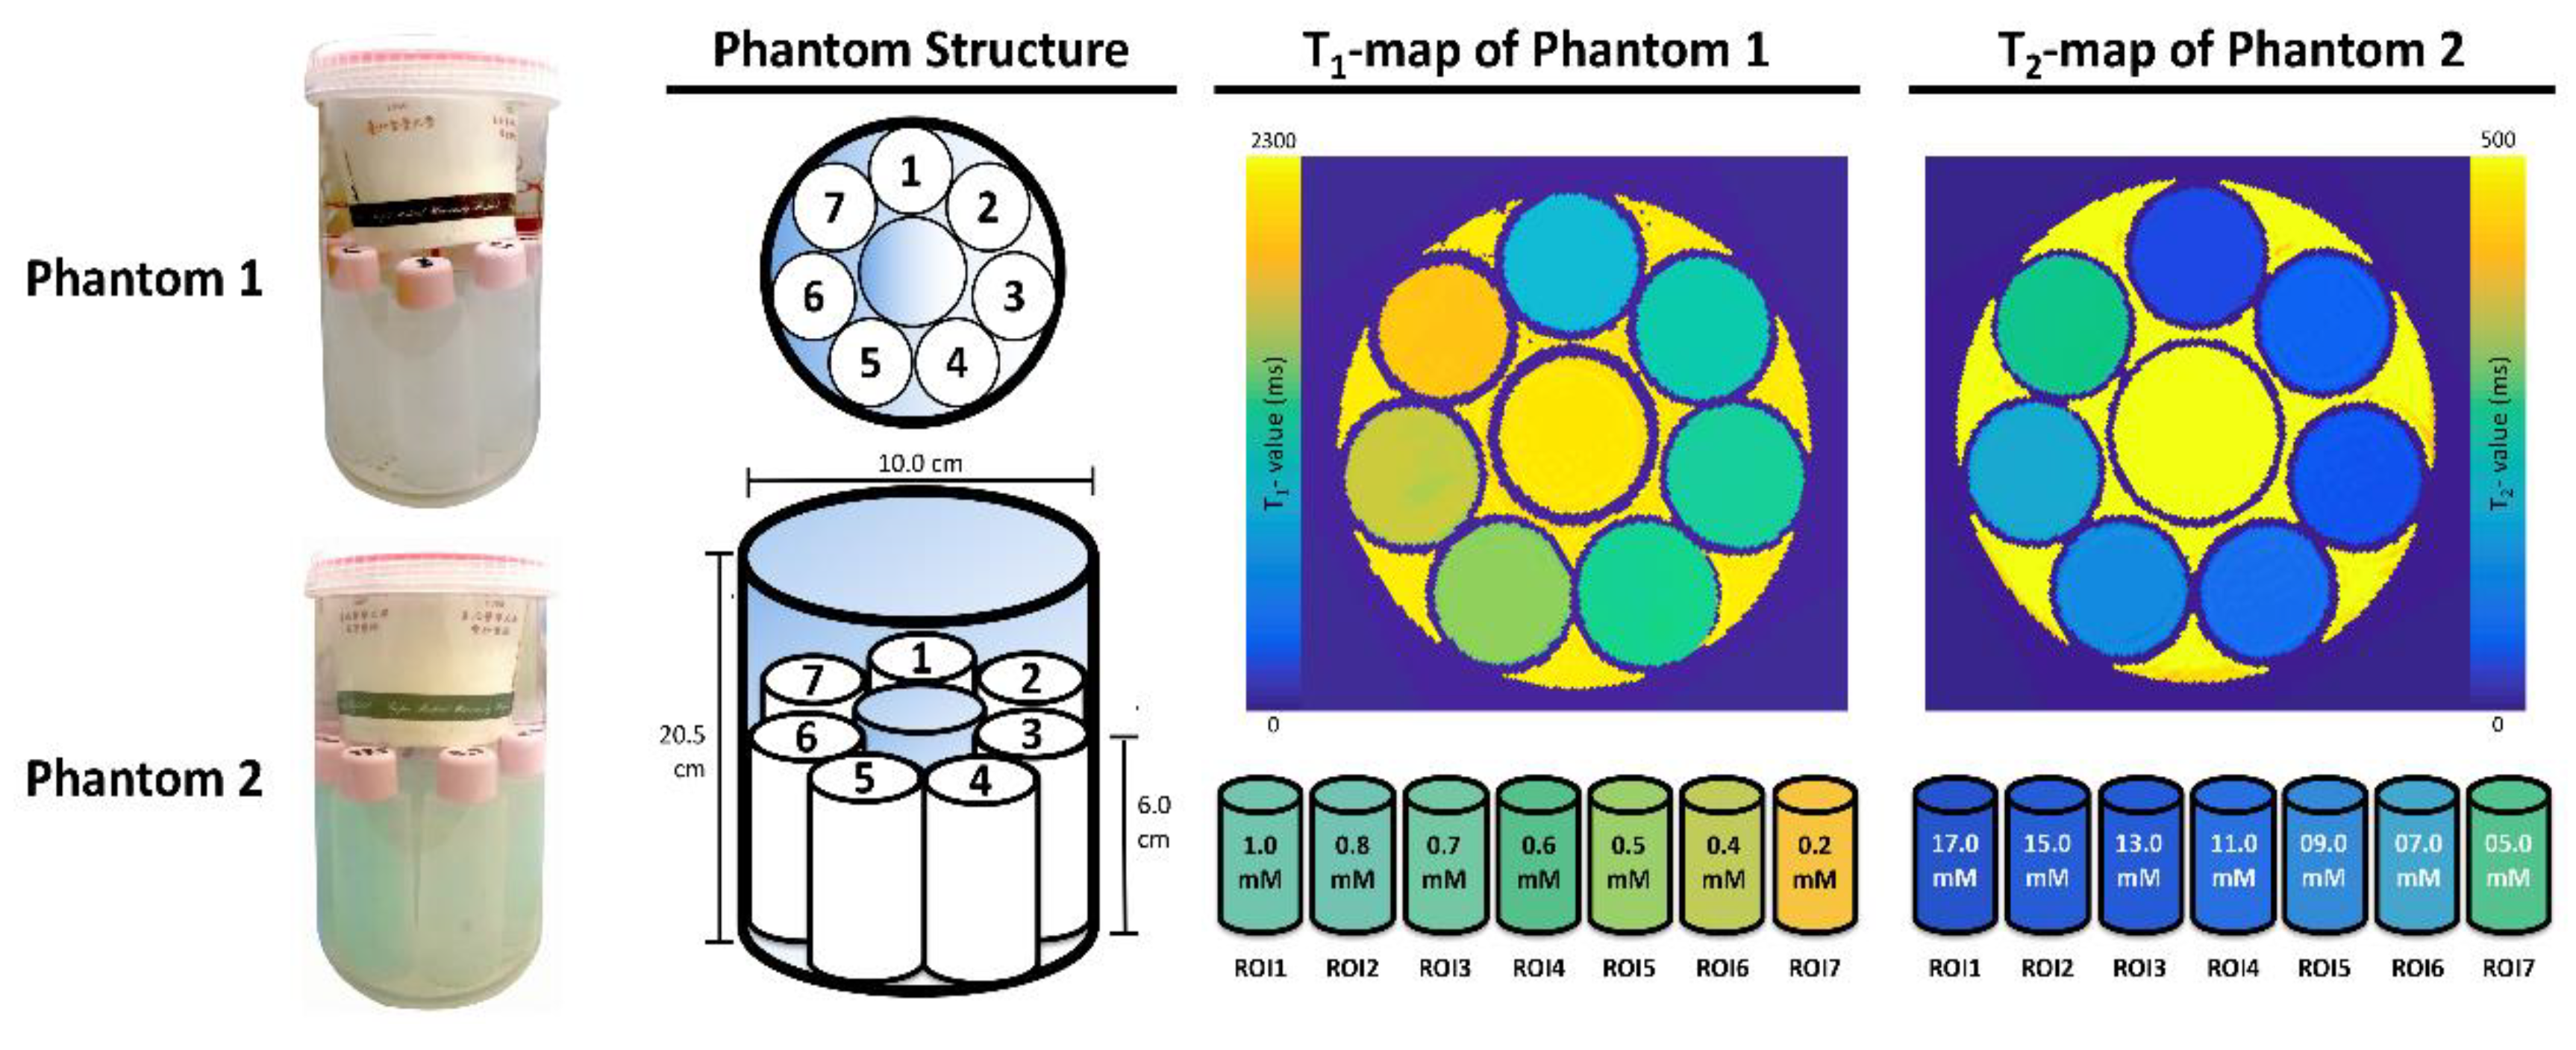

2.2. Specifically Designed Phantoms

2.3. Phantom Evaluation

3.1. Phantom Evaluation